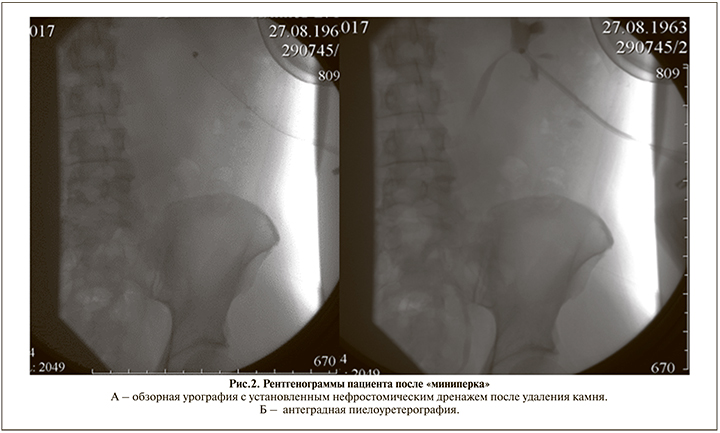

Выполнена миниперкутанная нефролитотрипсия с полным удалением камня (результат операции на обзорной и антеградной пиелоуретерографии (рис. 2А и 2Б). Операция закончена дренированием посредством нефростомии.